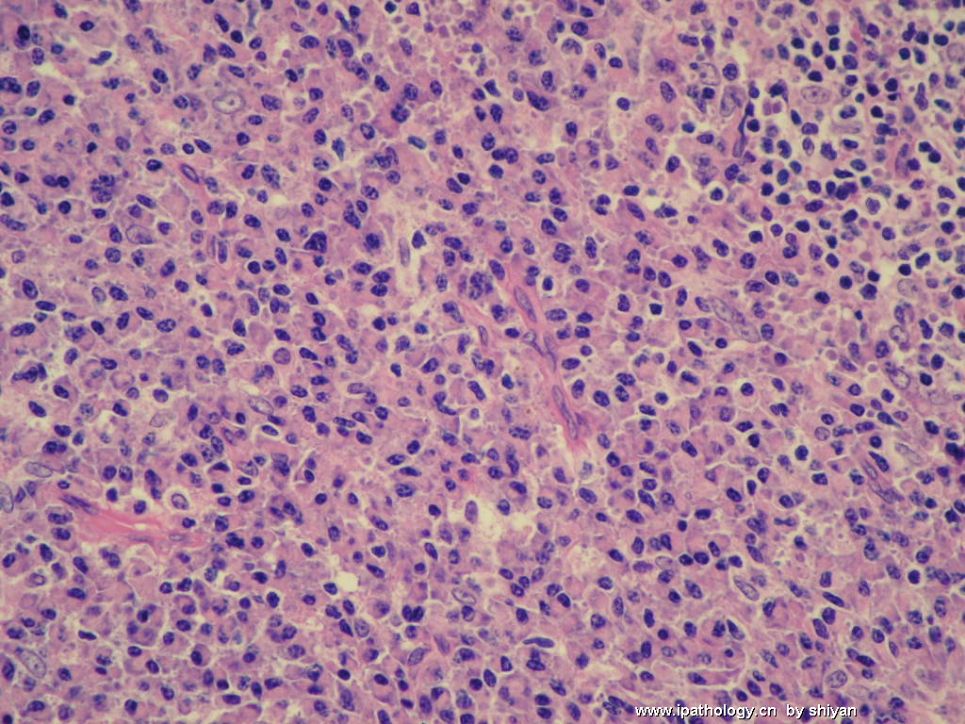

姓    名: ××× 性别:  女 年龄:  30

简要病史:  便血2月,一周前肛管活检,直径1.5cm。无淋巴结肿大,无发热等不适,肝脾不大。

基本符合浆细胞瘤。

部位特殊,部分息肉状,但 从形态上和累及深度及范围来看,要考虑浆细胞瘤。组化标记单克隆性吗?

形态上浆细胞较成熟且单一,免疫表型也支持浆细胞,且Kappa阳性细胞远多于Lambda阳性细胞数量,提示为单克隆性,所以结合形态和免疫表型,此例应该考虑浆细胞瘤的诊断。

形态上为较单一的浆细胞,符合浆细胞瘤的改变,但是该病人较年轻,30岁,骨外浆细胞瘤少见,排除MALT淋巴瘤,伴浆细胞分化。

最后诊断:(肛管)息肉状浆细胞单克隆增生,基本符合浆细胞瘤。